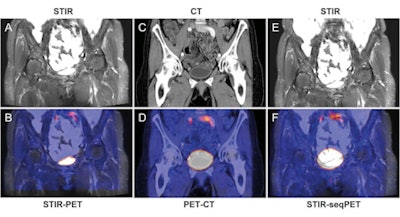

Simultaneous MR images included 3D T1-weighted fast low-angle shot (FLASH) and coronal T2-weighted short-tau inversion recovery (STIR) sequences in the abdomen. In the thoracic region, coronal STIR and coronal T1-weighted 3D gradient-echo sequences were conducted.

For the abdominal regions, regardless of the modality, the researchers found the greatest image misalignments in the bladder (mean, 9.6 mm ± 6.6), followed by the liver (mean, 9.0 mm ± 5.6) and the spleen (mean, 8.7 mm ± 5.4).

The mean image misalignment was 5.8 mm (± 2.8) for all organs in simultaneous PET/MRI, compared with 7.2 mm (± 5.1) for PET/CT and 11.9 mm (± 6.3) for MR images retrospectively fused with PET data from PET/CT.

The analysis of single organs showed no significant differences between STIR PET/MRI and PET/CT in the upper abdominal organs, although STIR PET/MRI showed the least misalignment in the liver, spleen, and right kidney.

The alignment of all upper abdominal organs was significantly better with STIR PET/MRI than with sequential STIR PET/CT. In the bladder, the alignment was significantly more accurate with STIR PET/MRI than with PET/CT and sequential STIR PET/CT.

Based on the results, the authors concluded that the alignment of hybrid datasets acquired in simultaneous PET/MRI was more accurate than with retrospective fusion for all abdominal organs. In addition, alignment with simultaneous PET/MRI was more accurate than with PET/CT in the urinary bladder.